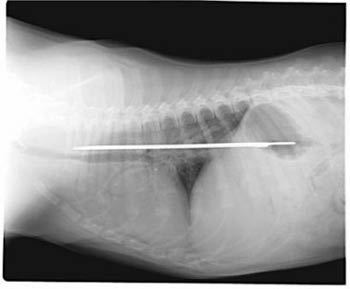

This photo of an X-Ray provided by Imperial Point Animal Hospital in Fort Lauderdale, Fla., Saturday, Sept. 24, 2005, shows a 13-inch serrated knife that somehow was swallowed by 'Elsie' a 6-month-old Saint Bernard puppy. [AP] |

Elsie, a Saint Bernard puppy, apparently had the blade between her esophagus and stomach for about four days before it was removed earlier this week in a 2-hour operation.